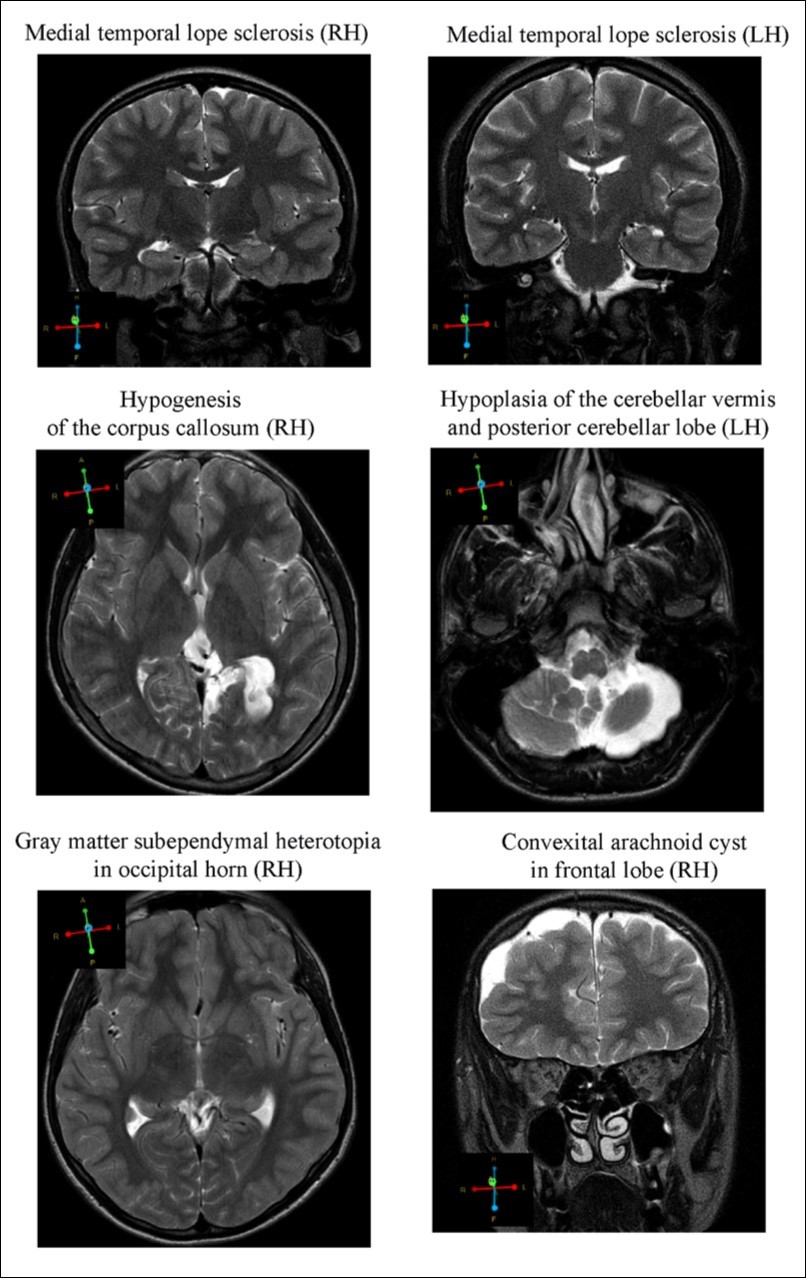

MR images revealed alterations in brain tissue only in boys with CD (n = 10), however there was no statistical significance between brain malformation and CD. Cerebral dysgenesis was the most prevalent brain abnormality. CD subjects displayed (Figure 2); 1. Medial temporal lobe sclerosis (hypotrophy of either right or left hippocampus) (n = 2); 2. Hypogenesis of the corpus callosum i.e. the band of white matter connecting the two hemispheres of the brain, failed to develop normally and was thinner than in healthy subjects (n = 1); 3. Gray matter heterotrophy, a type of cortical dysplasia, which results in the mislocation of neurons during neuronal migration (n = 2); 4. Arnold-Chiari malformation type II, characterized by a downward displacement of the cerebellar tonsils (hypoplastic cerebellum) through the foramen magnum (n = 1); 5.Arachnoid cysts in the temporal lobe and frontal convex (n = 2). All but two of the subjects described above had mothers with a history of stress and/or various complications during pregnancy and/or labor. Moreover, subjects with the described brain malformations showed signs of epilepsy and/or ADHD they have been excluded – in CD people. Only one subject, having corpus callosum hypogenesis and gray matter heterotrophy in the parietal lobe, showed mild neurological symptoms, having conduct disorder with intellectual disability

Figure 2.Representative images of the brain abnormalities observed in some children with the tendency of antisocial behavior (AST) by Magnetic Resonance Imaging (MRI). Coronal sections (4 mm thick) were acquired by T2 turpbo spin echo (TSE) multi vane (MV) sequence; Axial sections (6mm thick) - T2 TSE.